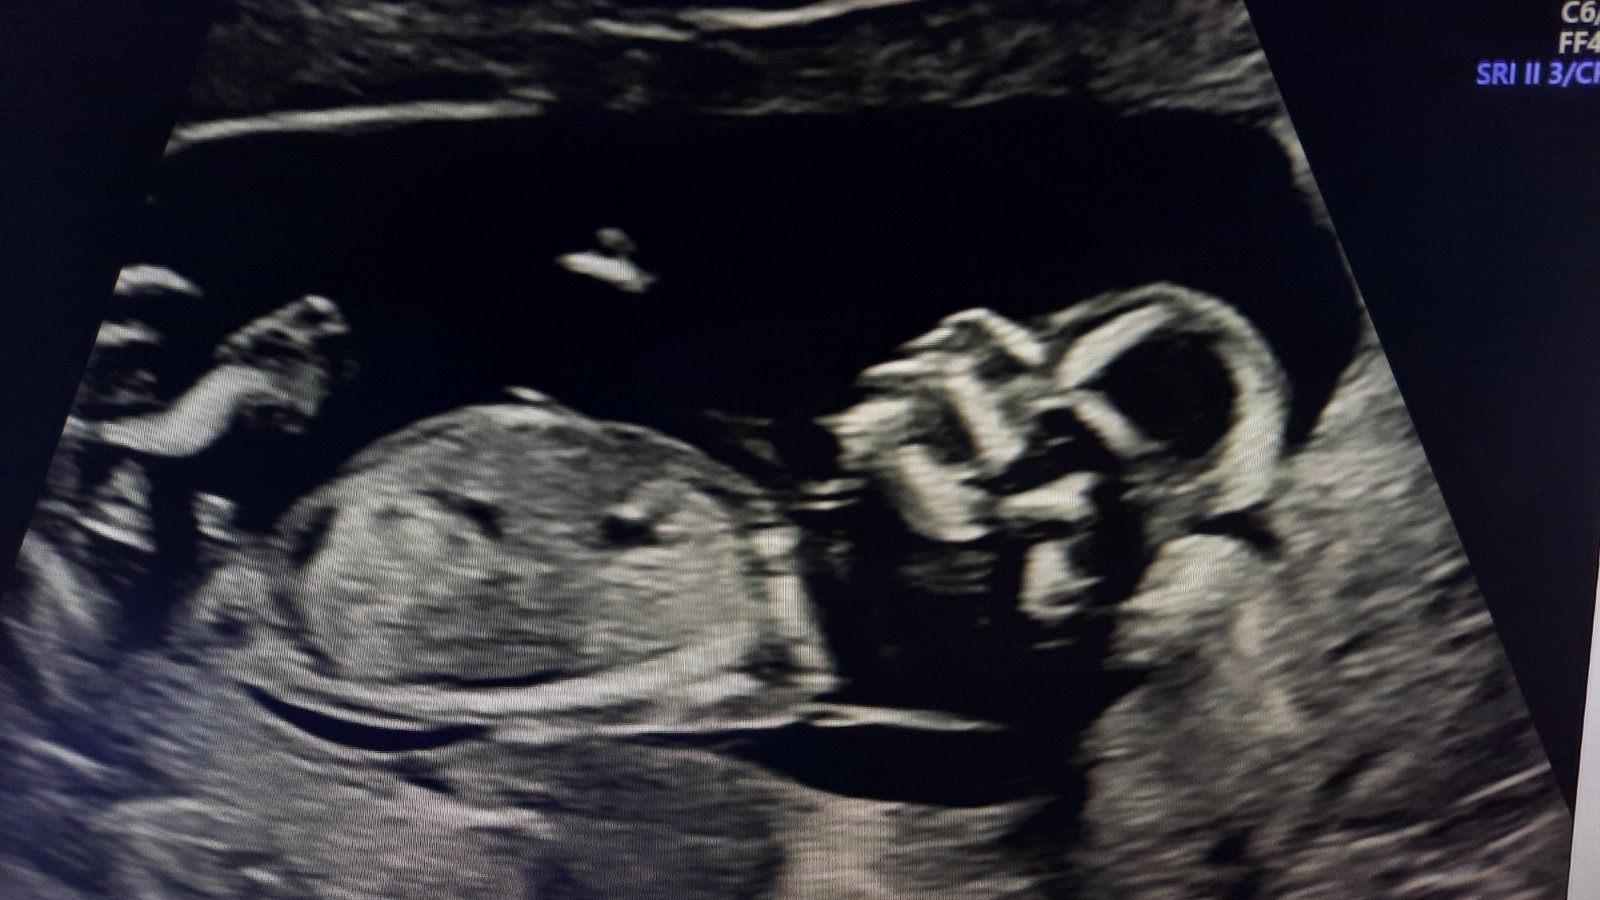

@cypercanka1 takto vyzera moj chlapcek zevraj

Vyzera to skor na chlapca🙂

chlapček 🙂